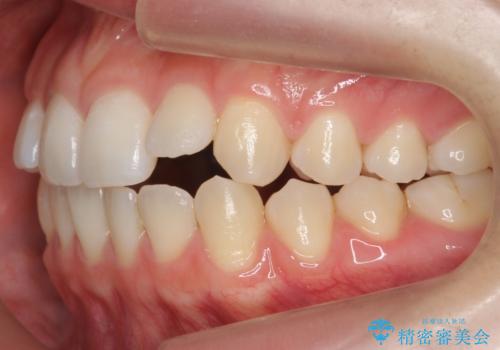

咬んでも向こう側が見える、前歯が閉じない症状でした。また、上の前歯が少し前に出ている状態でした。

上の前歯をわずかに削る処置を行い、後ろに下げながら下の歯となるべく咬むように矯正治療を行いました。